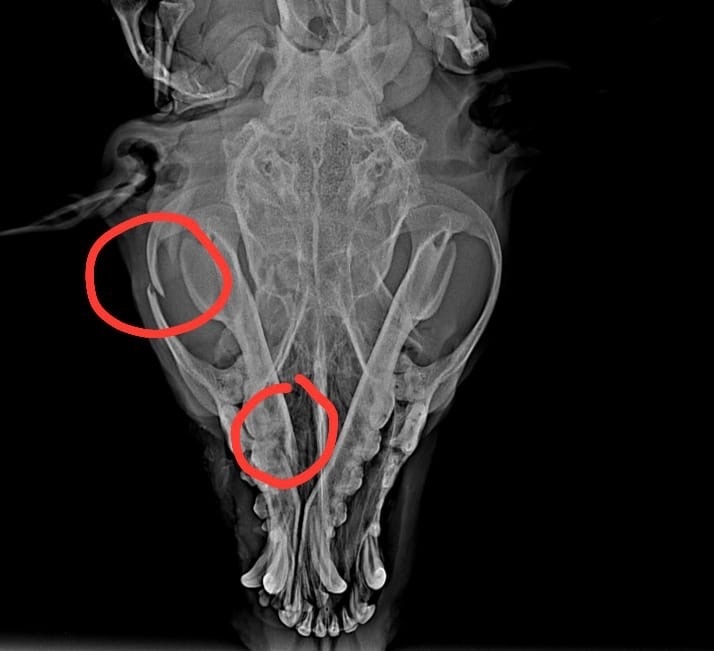

Открытый перелом нижней челюсти, костные обломки зияют в ротовой полости. Паралич задний конечностей, ПРИЧИНА НЕ УСТАНОВЛЕНА, возможно из-за ЧМТ. Позвоночный столб по рентген снимкам без видимых повреждений. Это все, что нам удалось выяснить и на что хватило денег. Снимков делали много, так как и челюсть и позвоночник проверяли. 7 штук вышло 8 400 рублей. ЭТО ОГРОМНАЯ СУММА, которой порой и в семье нет, а что говорить о приюте, где 500 бездомных таких же животных…